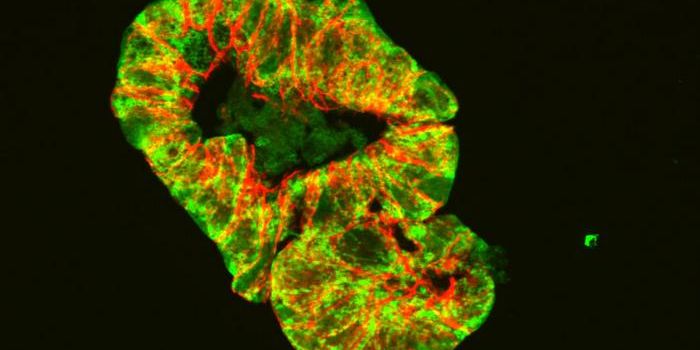

FEB 11, 2025Drug Discovery & DevelopmentResearchers have developed light-sensitive chemicals that can eliminate tumors in vivo in mouse models of breast cancer ...